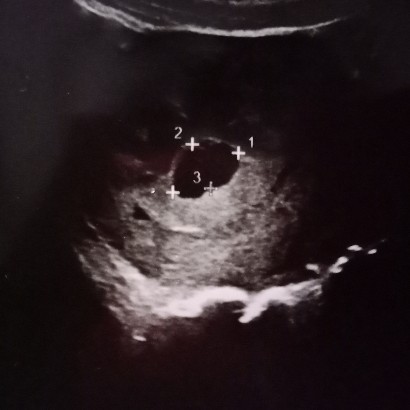

รกผิดปกติ

วันนี้มาซาวด์ดูเด็ก จากที่คำนวนว่า10วีค ซาวด์ดูได้6วีคค่ะ และรกหนาผิดปกติ เจอตัวน้องตอนซูมที่ยังมีหางเหมือนลูกอ๊อด ใครเคยเป็นแบบนี้บ้าง ไม่รู้ว่ารกหนาจะเป็นอันตรายกับลูกมั้ย ฟังหมอเข้าใจบ้างไม่เข้าใจ อารมณ์มันห่วงน้องไปหมด หมอพูดประมาณว่าถ้ามีเลือดออกให้รีบมาหาหมอ เพราะรกที่หนาทำให้แม่ตกเลือดมากกว่าปกติ เสี่ยง ตอนนี้ขออย่างเดียวขอให้ดวงใจแม่แข็งแรงสมบูรณ์ก็พอ